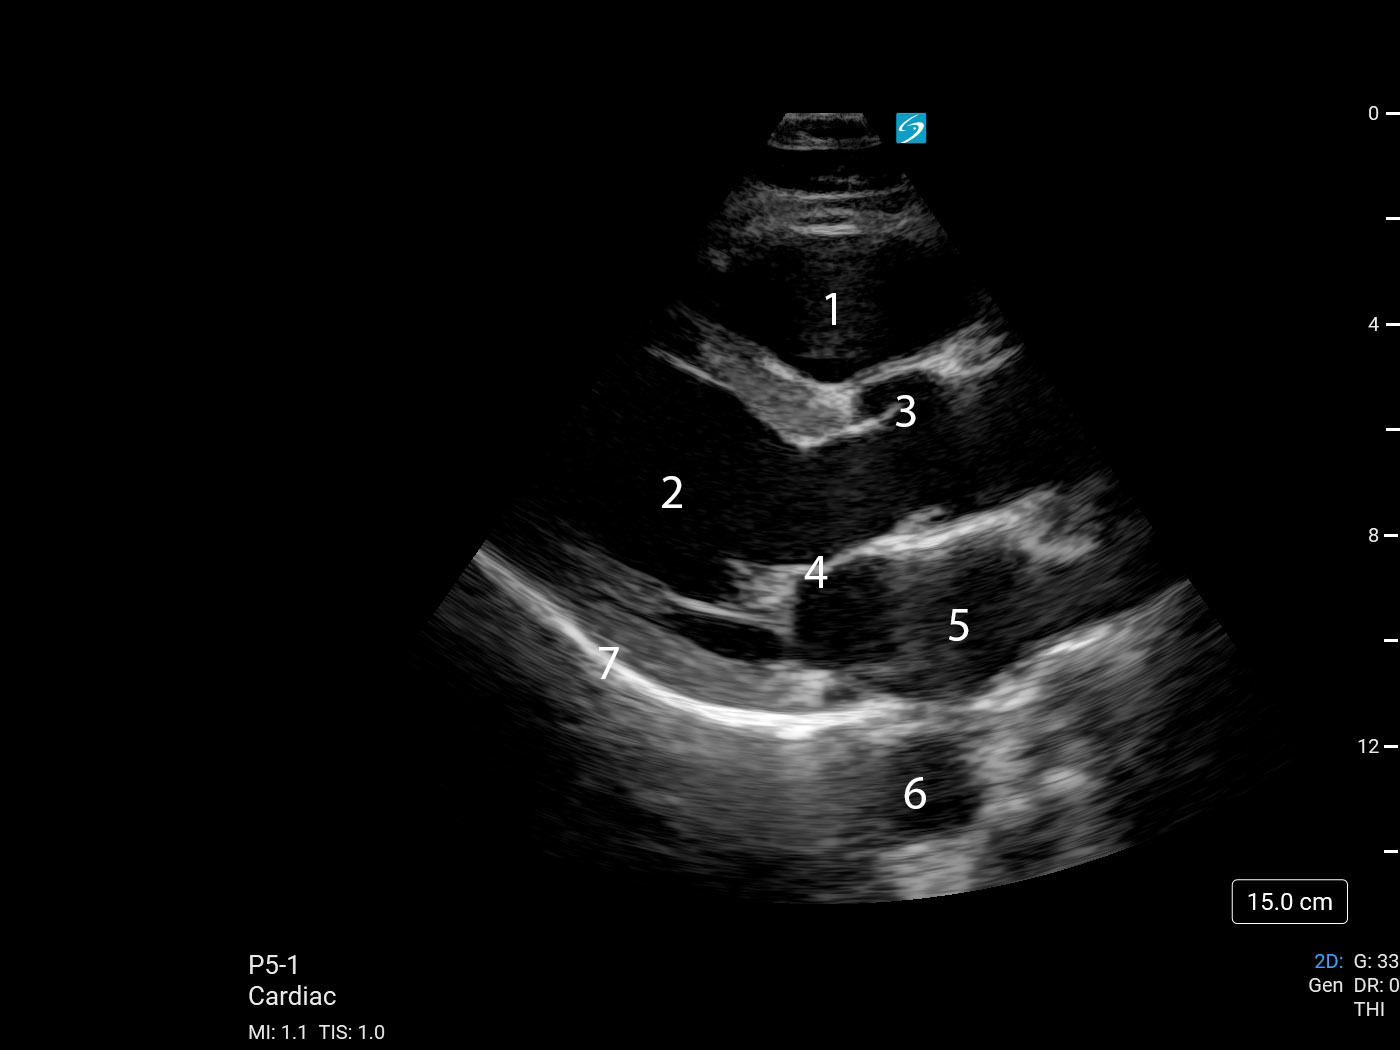

Heart Parasternal Long Axis (PLAX) (Sonosite PX P5-1) 1 Image

1. Right Ventricular Outflow Tract (RVOT)

2. Left Ventricle (LV)

3. Aortic Valve (AV)

4. Mitral Valve (MV)

5. Left Atrium (LA)

6. Descending Thoracic Aorta (DTA)

7. Pericardium